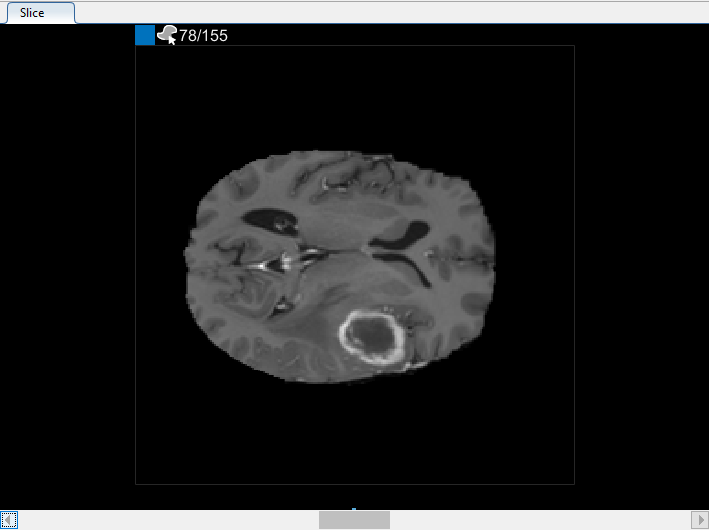

Можно также просмотреть каждый срез объема на панели « Срезе». Для перехода от среза к срезу используйте ползунок в нижней части панели. Вы можете увидеть опухоль на срезе 35 через срез 88. По умолчанию на панели « Срезе» отображается том, ориентированный вдоль оси X-Y, но изменить его можно с помощью кнопок в разделе Ориентация (Orientation) панели инструментов на вкладке Сегмент (Segmenter). Панель « Срез» также находится там, где для определения маски используются инструменты рисования.

После использования интерполяции проверьте отдельные срезы, чтобы увидеть, создала ли интерполяция удовлетворительные ROI. Обратите внимание, что информация только для чтения на срезе 71 не заполняет весь объект, который вы хотите сегментировать. Настроить информацию только для чтения можно вручную с помощью инструмента «Кисти краски». Также можно использовать один из инструментов на вкладке Automate. Например, можно использовать Active Contours, чтобы вырастить ROI на срезах, где он не заполняет полный размер опухоли. Можно также использовать Алгоритм Добавления, чтобы задать свой собственный алгоритм для работы с ROIs.